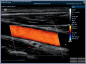

Neben einem ausführlichen Gespräch, der Anamnese, Zeit und Zuwendung gehören auch die Anwendung von wissenschaftlich evaulierten diagnostischen Verfahren zu einer guten Eingangsuntersuchung. Ich freue mich Ihnen in meiner Praxis deshalb nun auch die Ultraschalluntersuchung mit modernster Technik, einem mindray Consona N6 anbieten zu können.

- Darstellung der Schilddrüse - Darstellung der hirnversorgenden Gefäße mit Messung der Intimadicke (IMD) - Ultraschall des Herzens z. B. Stenose / Dichtigkeit der Herzklappen, Wandbewegungsstörungen,... - Ultraschall des Bauchraumes wie Leber, Gallenblase, Nieren, Blase, Milz. - Gefäßdarstellung

Video Farbdoppler der Halsarterie zur Darstellung der Durchblutung Video Farbdoppler der Niere zur Darstellung der Durchblutung Video Herzultraschall eines gesundes Herzens mit guter Pumpfunktion Video Herzultraschall mit eingeschränkter Pumpfunktion und vergrößerten Vorhöfen Video Herzultraschall bei Herzinsuffizienz und undichter Herzklappe